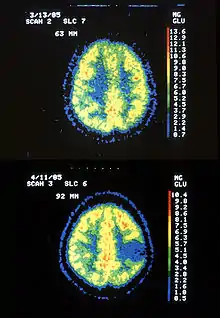

و هذه بعض التصويرات بالرنين المغناطيسي التي تكشف عن بعض الحالات الشائعة من الورم النجمي :

عينة مرضية من الورم النجمي .